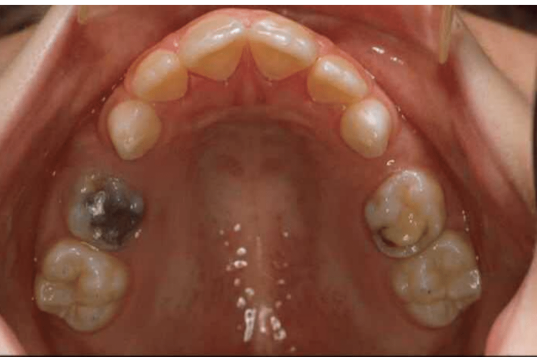

what age is this patient

6 or 7

which other permanent teeth should be present at this time

first permanent molars (6s)

what is the name given to the space between the upper central incisors

midline diastema

what has caused this in this particular case

low frenal attachment

what is the likely cause of the general appearacnnce of the lower central incisors

fluorosis

how is fluorosis likely to have arisen

excessive ingestion of fluoride during development of the teeth

what other permanent teeth are likely to affected by fluorosis

upper centrals

lateral incisors

canines

first premolars

second premolars

first molars

give 3 tx options for lower central incisors

microabrasion

composite restoration

strip crowns

which primary teeth are still present

55

54

53

63

then adults 16, 12, 11, 21, 22, 25, 26